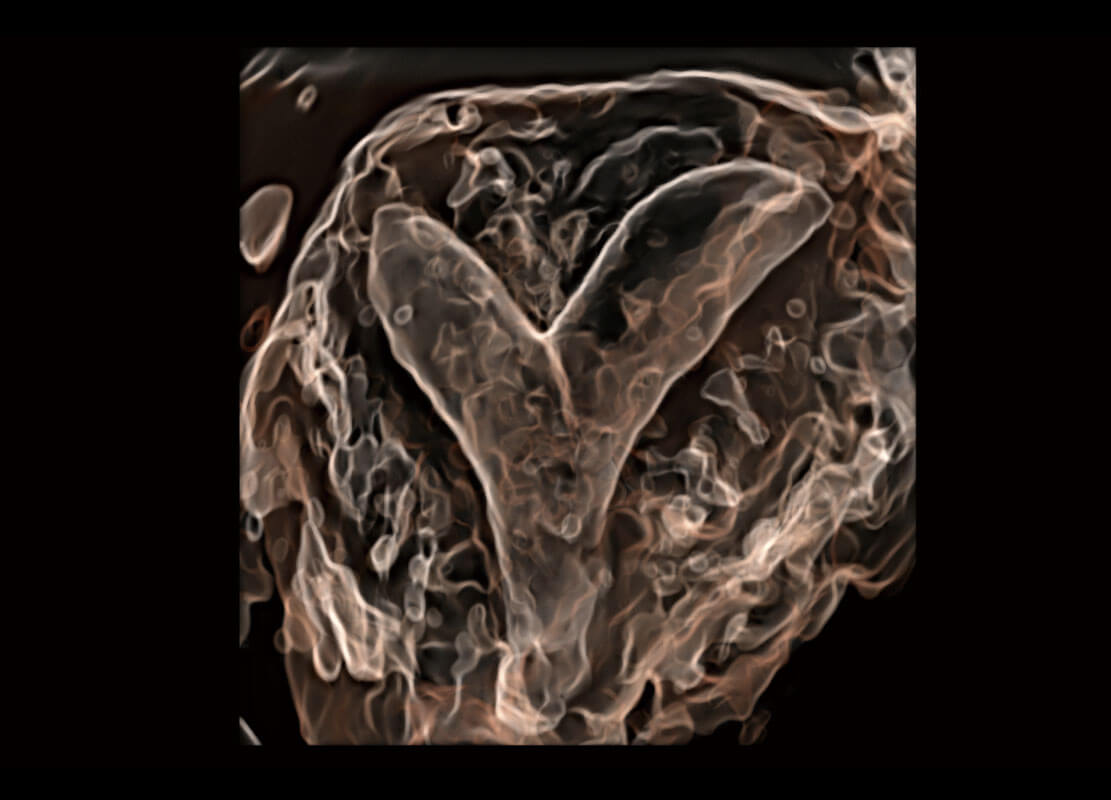

胎心容积成像